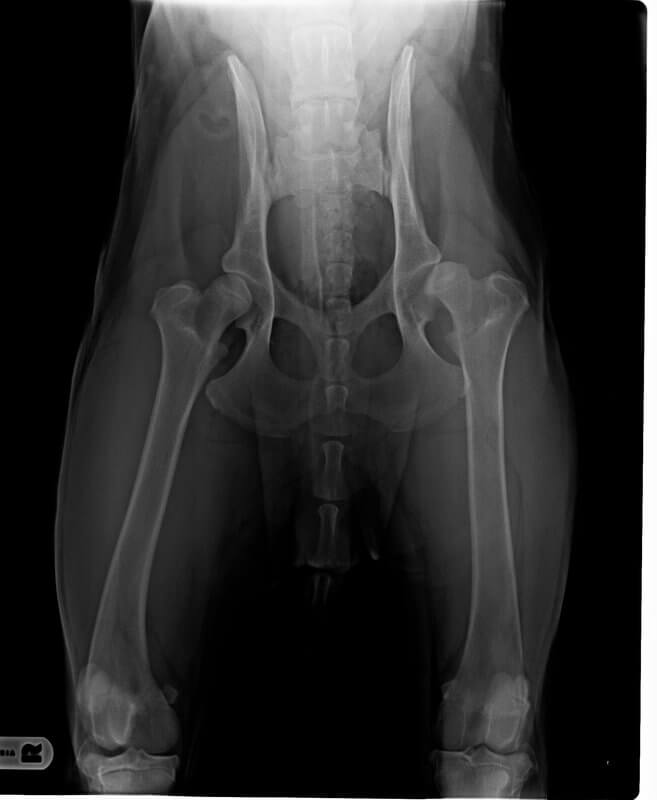

Ich vertraue nach etlichen Falschdiagnosen durch Röntgentierärzte nur noch dem Urteil von Dr. Tellhelm und einigen ganz wenigen anderen Experten. Weil es zudem auch wirklich nicht die Welt kostet. Ich könnte jetzt gar nicht aufzählen wie häufig ich es bereits erlebt habe dass er wirklich krasse Fehldiagnosen durch andere Tierärzte richtig stellen konnte. Weil er halt auch sofort erkennt wenn ein Röntgenbild technisch schlecht gemacht ist. Sei es weil die Belichtung nicht stimmt und/oder der Hund falsch gelagert wurde. Dann wird vorhandene Knochensubstanz u.U. auf dem Röntgenbild nicht richtig dargestellt. Oder der Norbergwinkel wird dadurch beeinflusst.

Muss aber halt jeder selbst wissen... Dr. Tellhelm ist halt ein Fachtierarzt für Radiologie, von denen es in Deutschland nur relativ wenige gibt (und nur eine Handvoll von denen hat sich auf Kleintiere spezialisiert; die meisten VetRadiologen sind Fachtierärzte für Pferde). Und Radiologen sind nun mal die Spezialisten im Bereich Röntgen/Röntgenauswertungen. Bei Dr. Tellhelm kommt eine wahnsinnig lange Berufserfahrung hinzu, und die explizit im Bereich der Skeletterkrankungen bei Hunden.